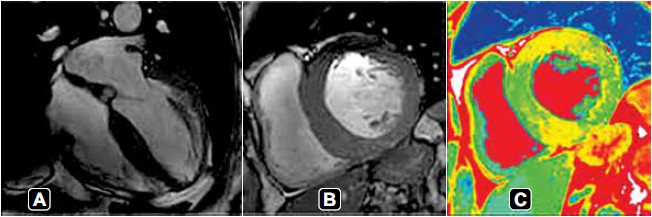

Durante investigação etiológica, realizou uma ressonância cardíaca, apresentada a seguir.

A principal hipótese diagnóstica é: